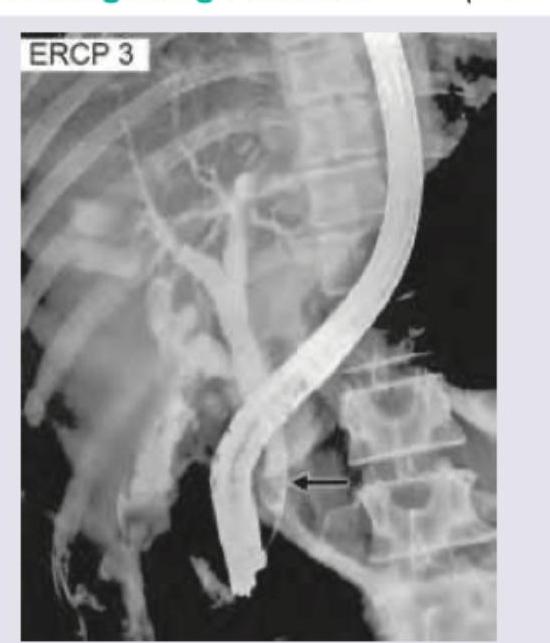

The image shows: (DNB Pattern 2018)

Explanation: ***ERCP*** - The image shows a **cannula** within the **bile duct**, indicating the injection of contrast medium directly into the biliary tree via the **ampulla of Vater** during an endoscopic procedure. - The presence of the endoscope clearly visible alongside the opacified bile ducts confirms that this is an **Endoscopic Retrograde Cholangiopancreatography (ERCP)**. *Percutaneous cholangiography* - This procedure involves inserting a needle directly through the skin and liver into a bile duct to inject contrast. - There is no visible **endoscope** or evidence of a **transhepatic** approach in the image. *Oral cholecystography* - This is an older, non-invasive method where oral contrast agents are absorbed and concentrated in the gallbladder. - The image clearly displays the **ductal system** and an **endoscope**, which are not typical features of oral cholecystography. *T-Tube cholangiogram* - A T-tube cholangiogram is performed through a surgically placed **T-tube drain** in the common bile duct, usually post-cholecystectomy. - The image does not show a T-tube in place; instead, it shows an **endoscopic instrument** at the ampulla.